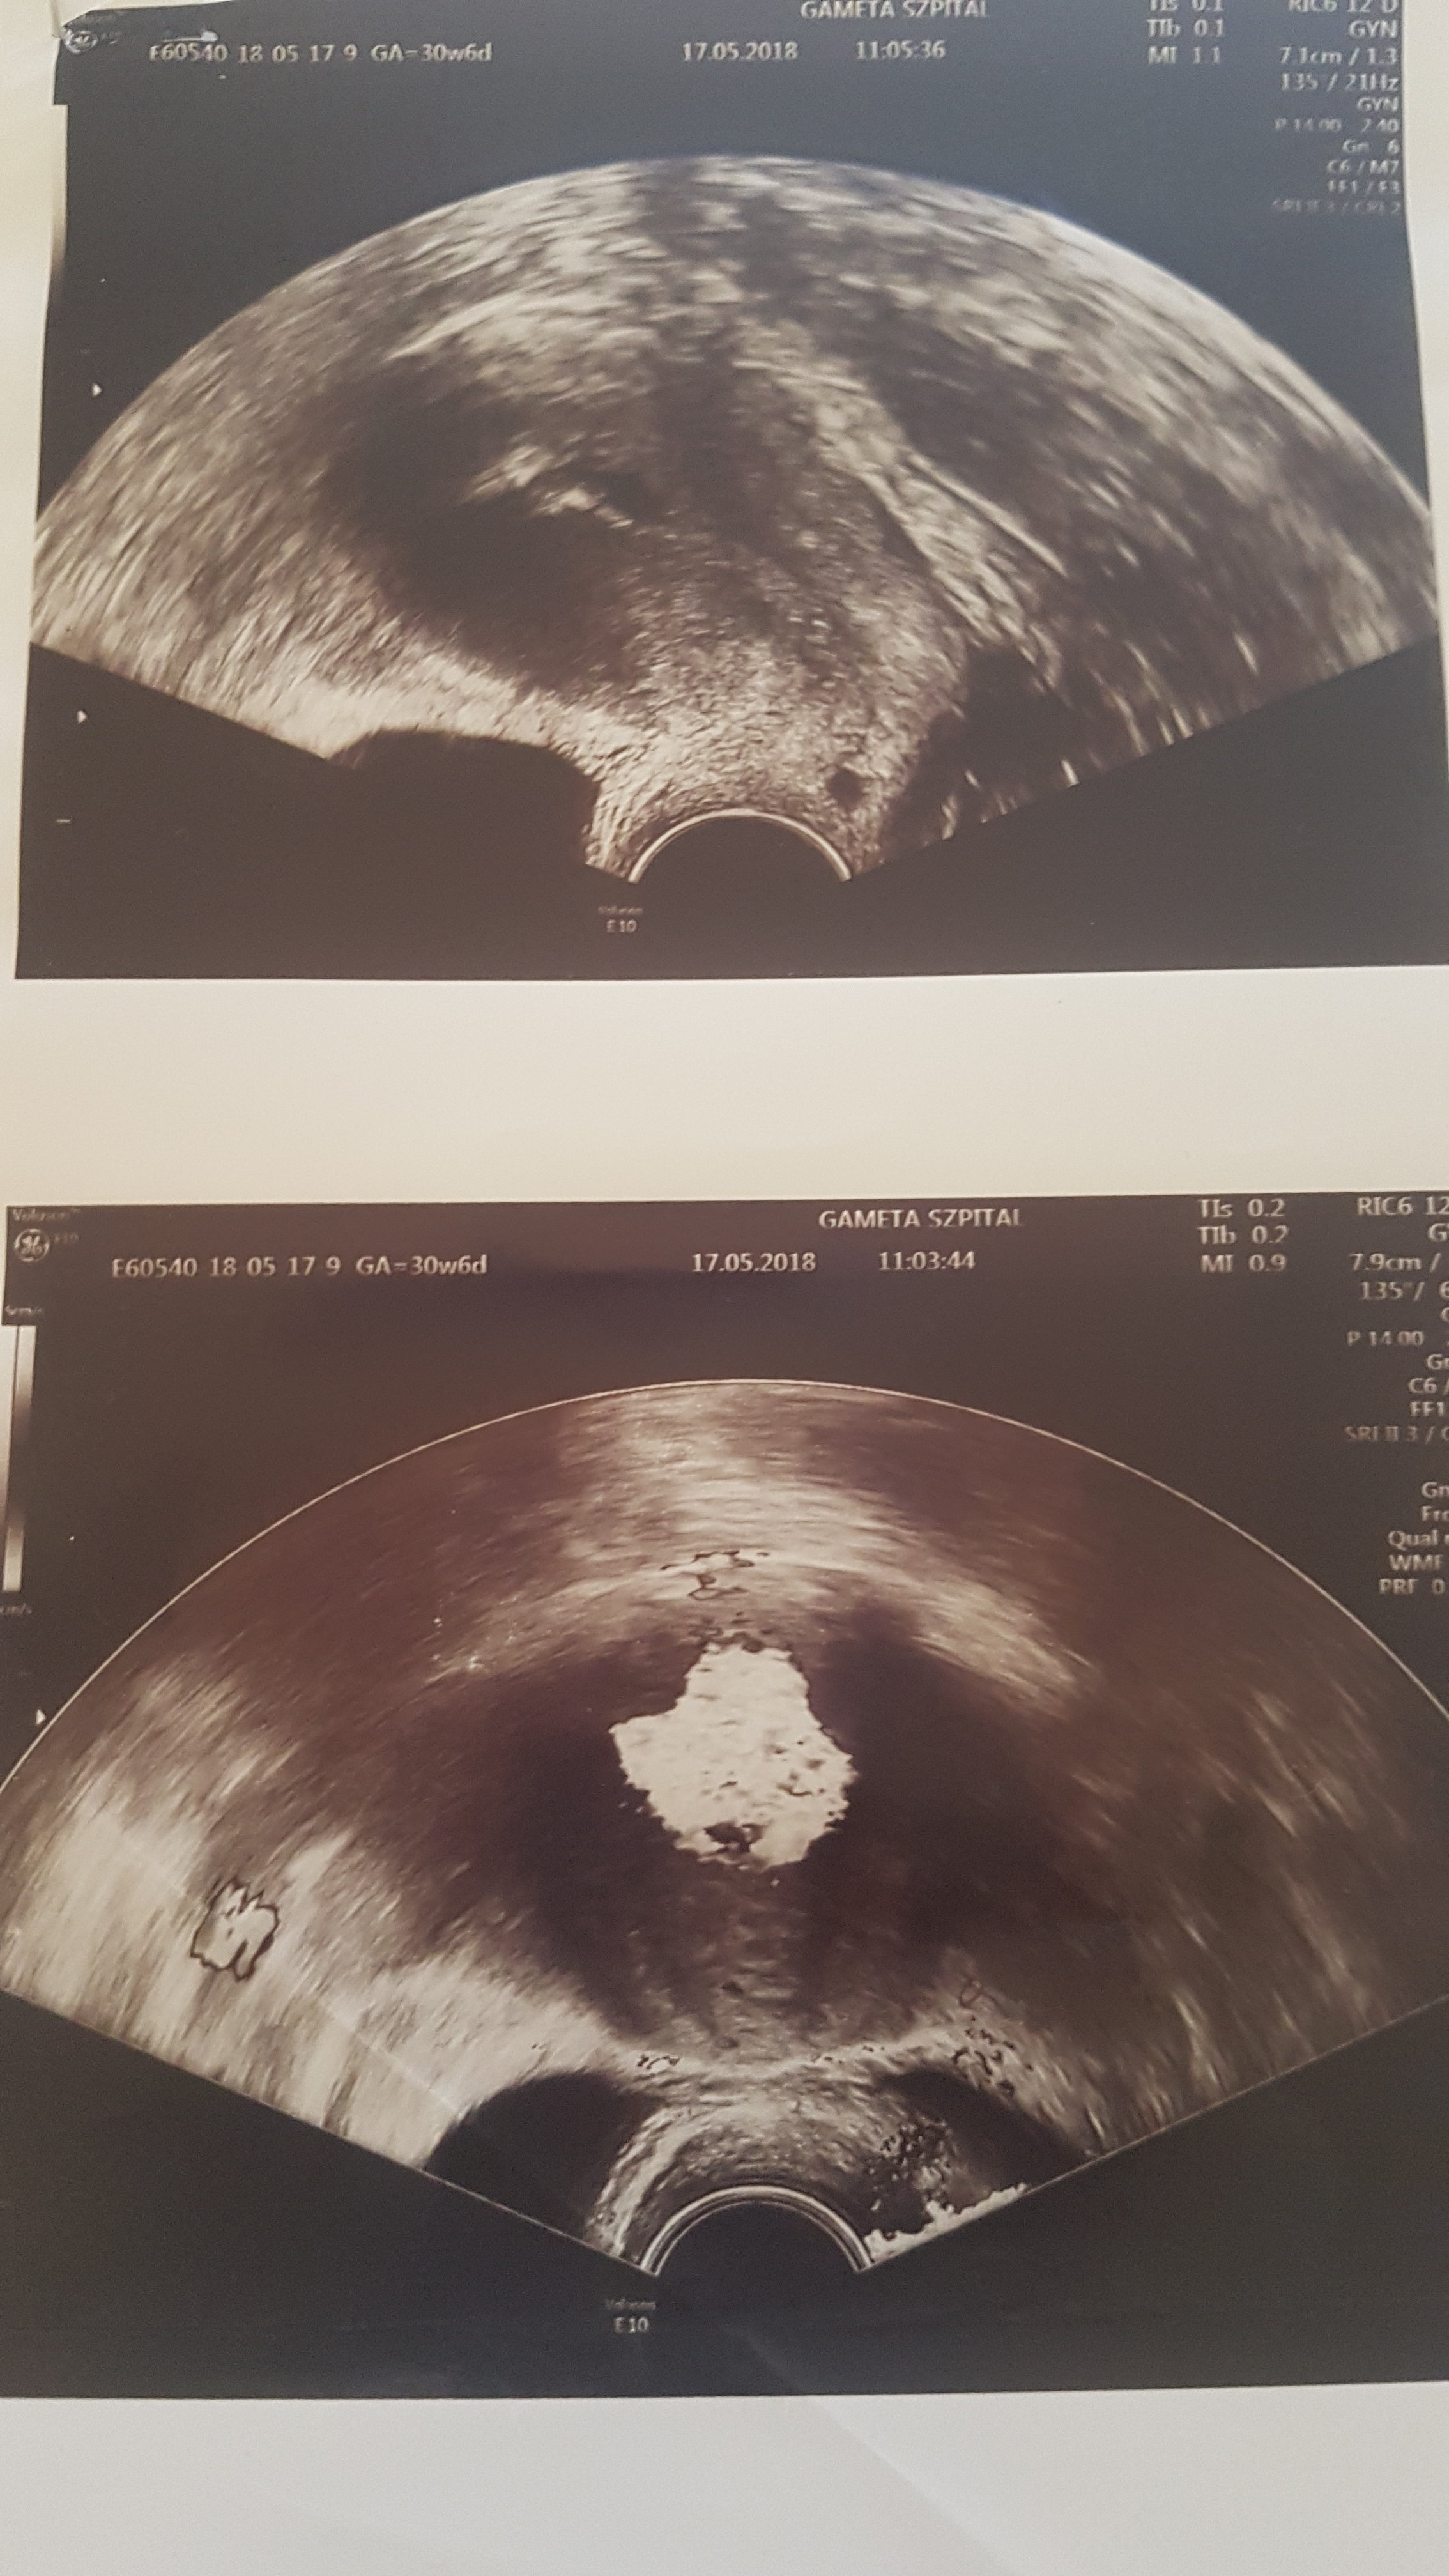

@motylek24 od razu znalazlam zdjecia z HSG, czy u ciebie tez to tak wygladało? Bo u nas podobne kliniki ;)